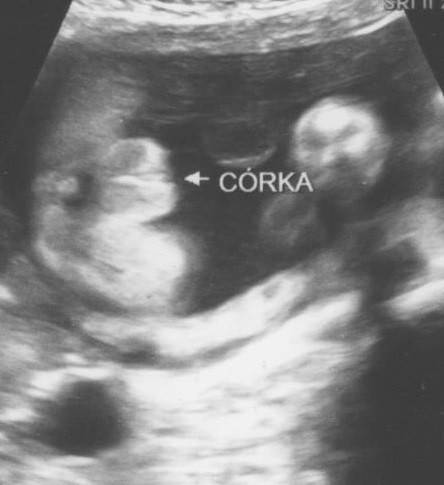

, ale zaraz lekarz rozwiał wątpliwości .